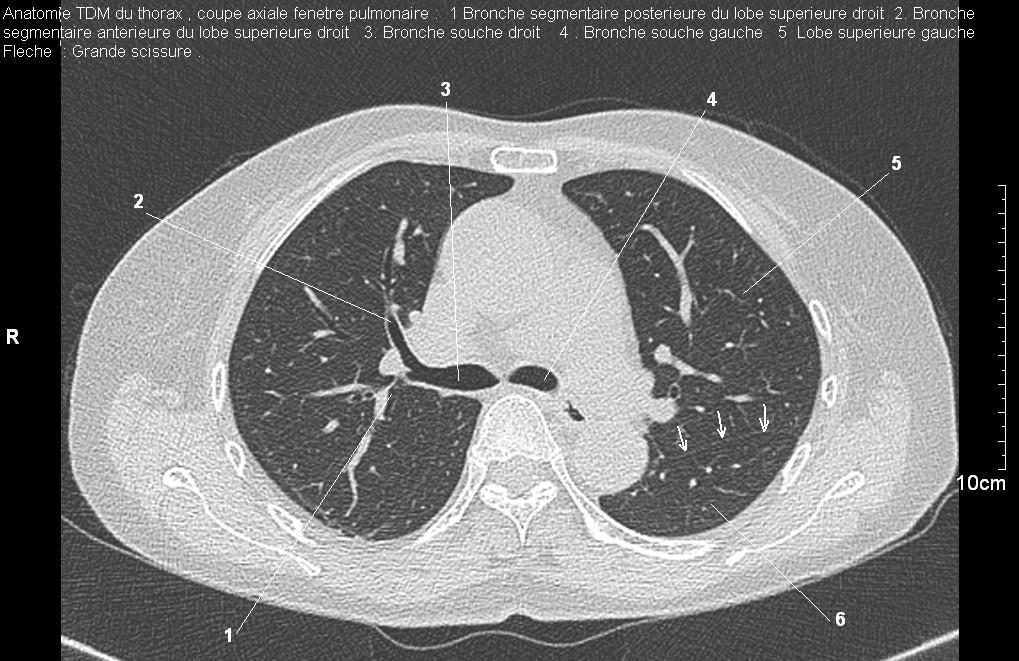

La TDM fenêtre osseuse et fenêtre

parenchymateuse : Normalement image radiologique TDM du

parenchyme pulmonaire de la fenetre mediastinale est moindre

de interprete et de detecte que la fenetre parenchymateuse ,

en excepte de l'explore des hiles et des vaiseaux . Sur les

coupes TDM fenetre parenchymateuse normalement on peut en

voyaient des scissure , des septals segmentaires et des

acinies même que les hiles , les vaisseaux hilaires

et ganglions lymphatiques .

Image radiologique TDM normale les hiles , les ganglions lymphatiques et le parenchyme pulmonaire ,

fenetre parenchymateuse : Aspect radiologique

du parenchyme pulmonaire peut être de

detecte et on peut en voyait des acinie , des septal

intersegmentaire , de scissure , des hiles , des

vaiseaux et des ganglions .